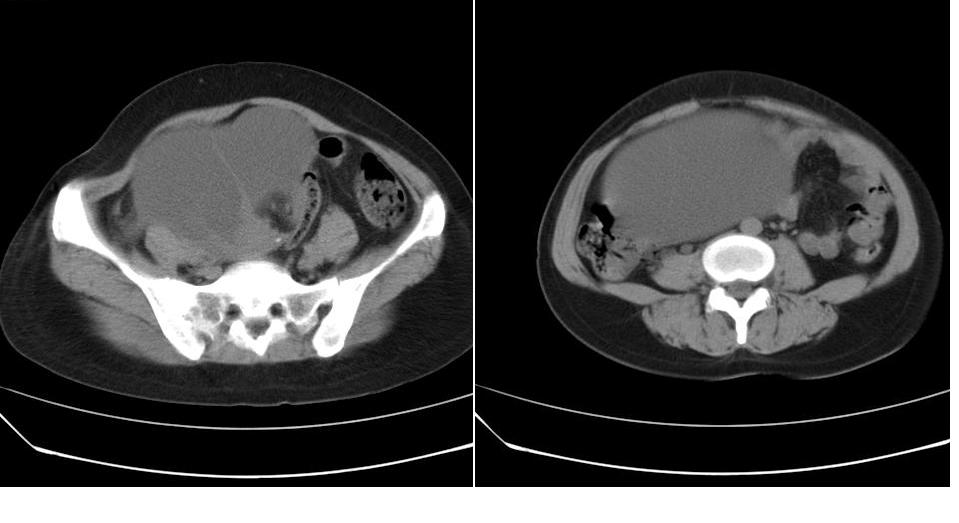

女 35岁,下腹部坠感疼,其它病史不详。图象顺序有点乱。

定位于盆腔附件,有囊性密度,有脂肪密度、还有骨密度;应该是比较典型的卵巢畸胎瘤。